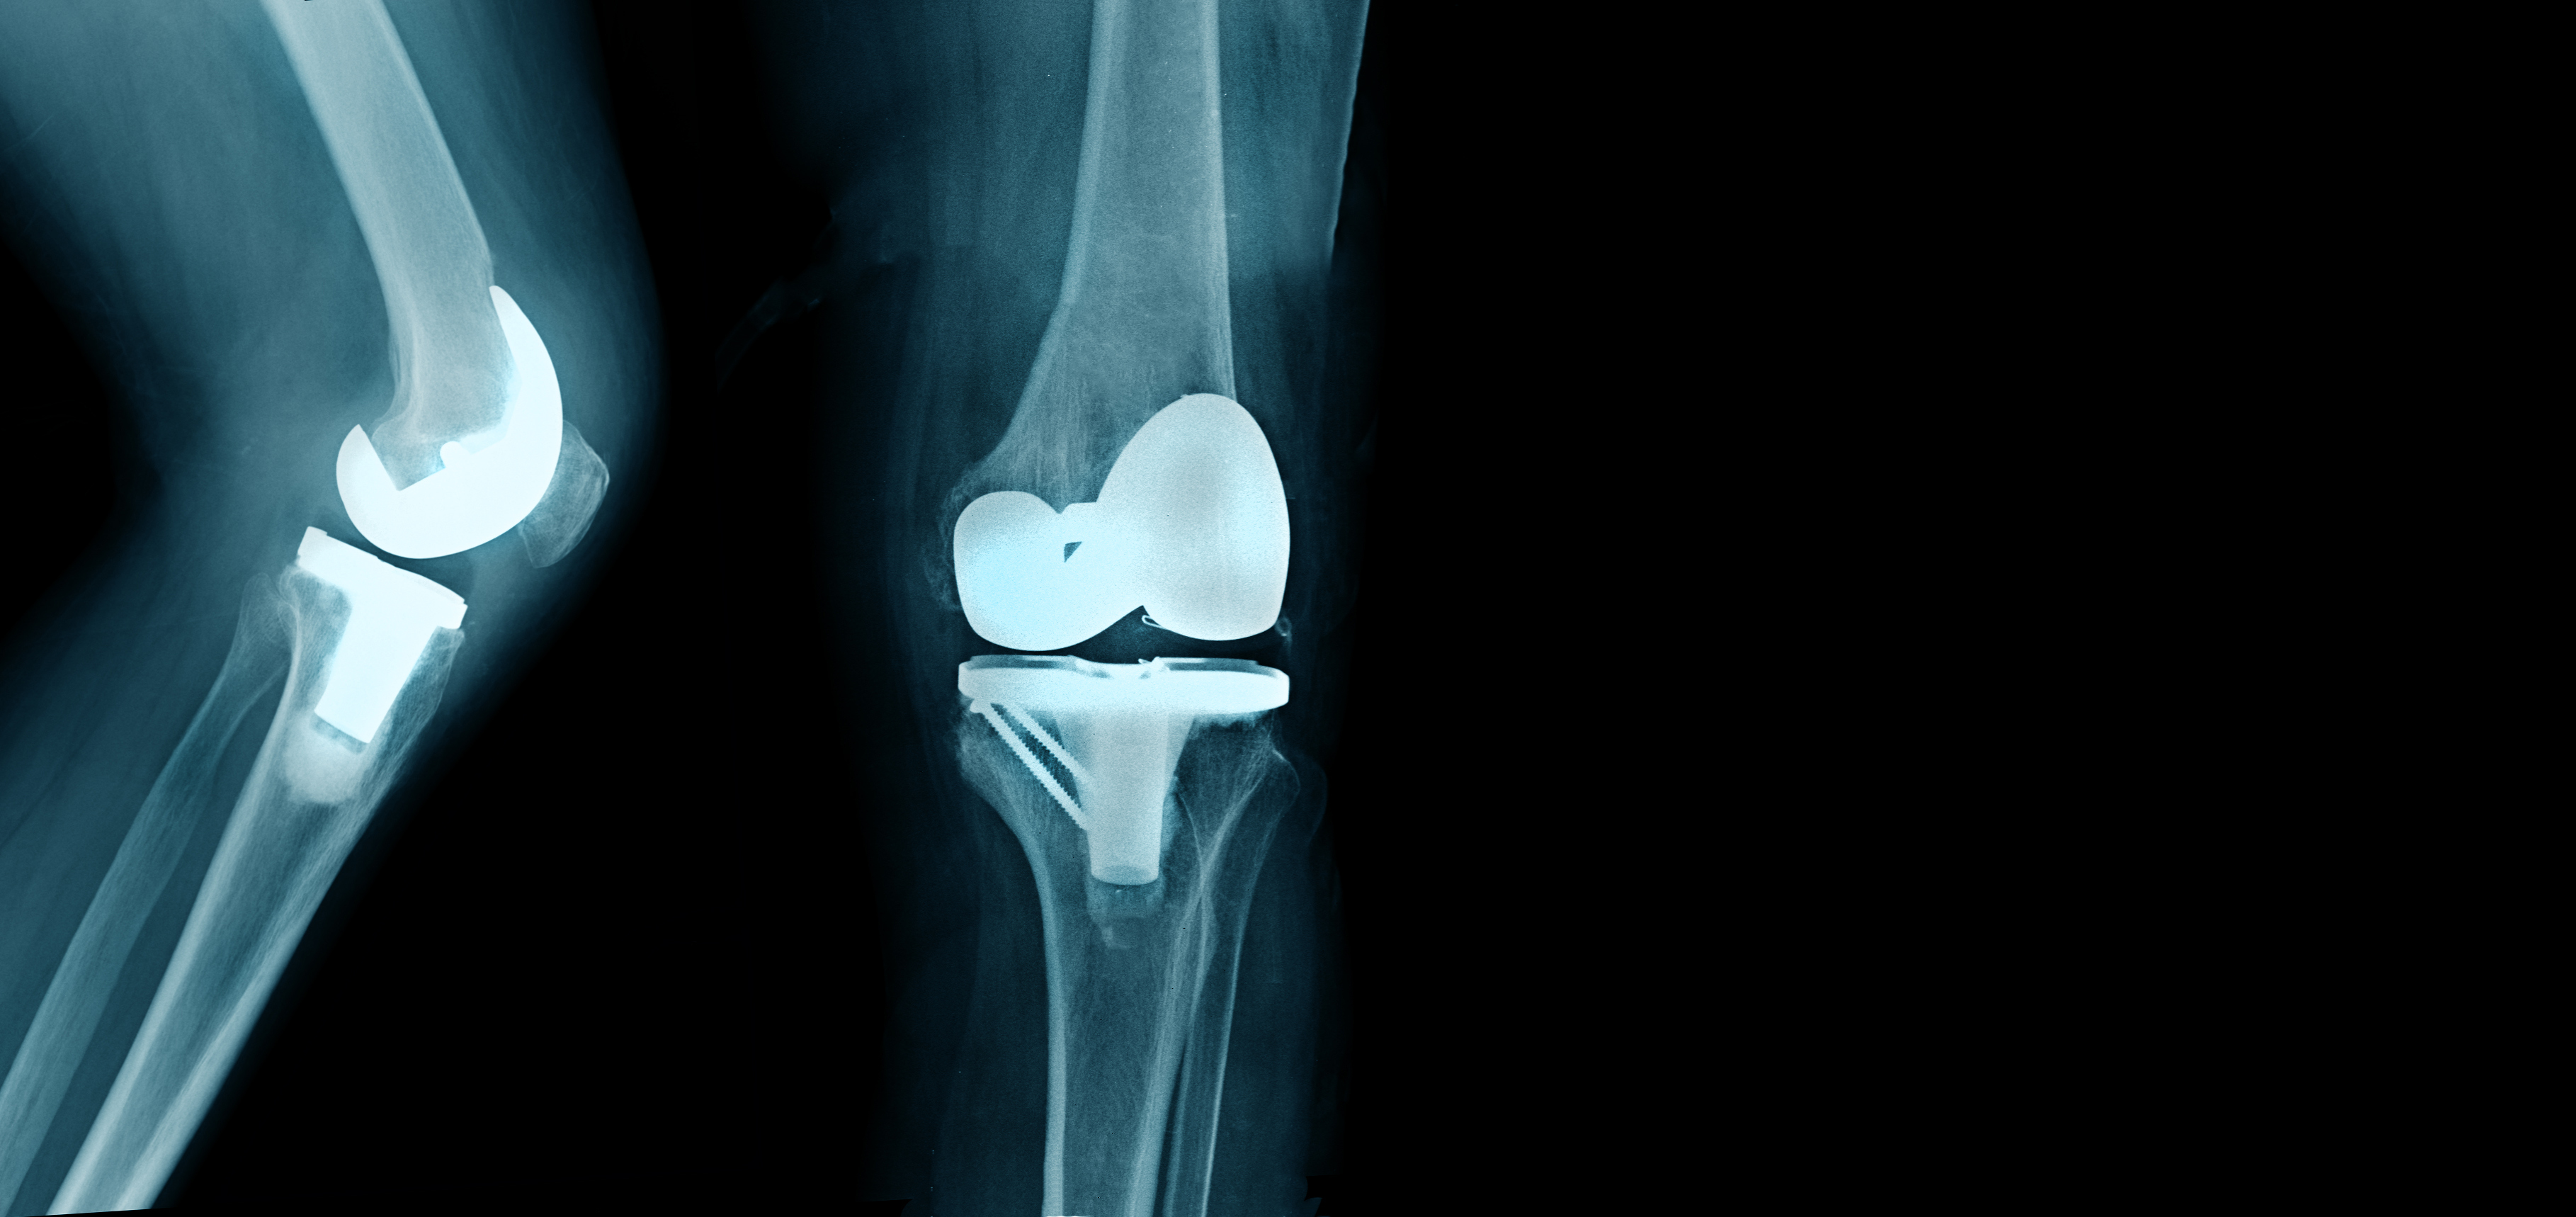

Thankfully, you can start preparing for your recovery before you even have the procedure. Experts suggest some lifestyle changes might improve your optimal outcome from knee or hip replacement surgery.